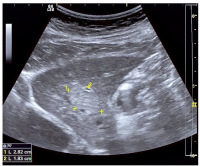

Abbildung

Rundherd der Leber

Abbildung 1: Sonographisch echokomplexer, mäßig echoreicher Rundherd der Leber im Lebersegment 2 (derselbe Herd wie in Abbildung 2 beschrieben).

Keywords: LeberLebersegment 2Rundherd